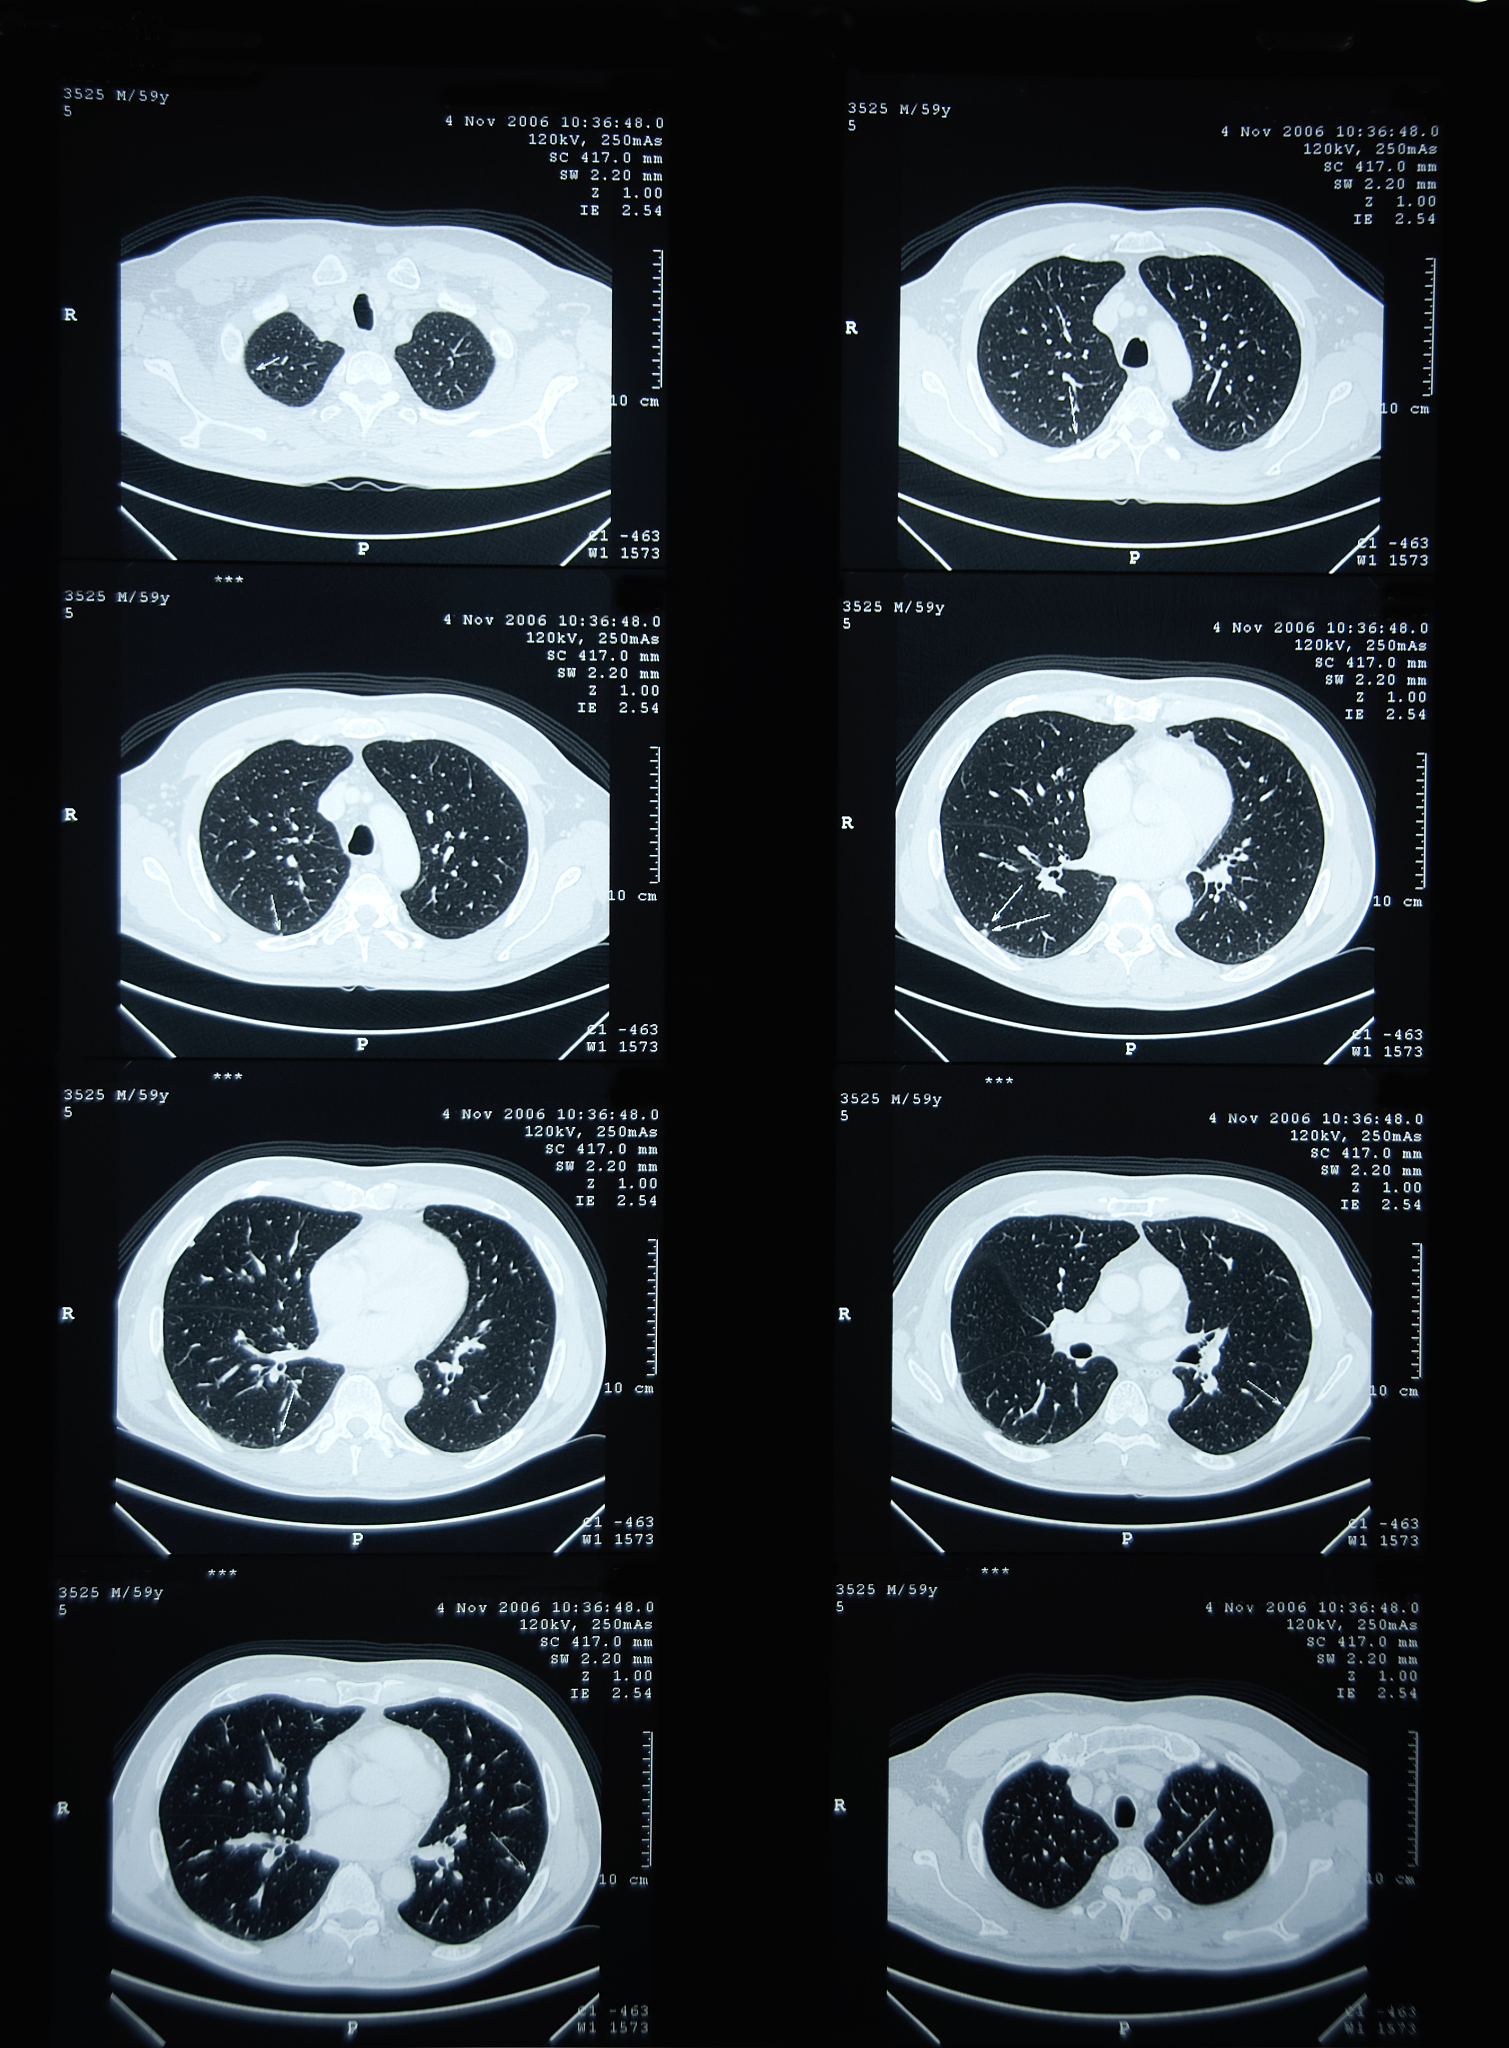

随着医学影像技术的进步和CT的广泛应用,现在能够更容易地发现难以在胸片上观察到的肺结节。肺结节是指肺部影像学上的一种特征,其表现非常相似,一般没有明显的自觉症状。大多数肺结节是良性的,只有一小部分被确诊为肺癌,然而,鉴别肺结节的良性与恶性仍然相当困难,特别是结节越小,诊断越困难,仅仅通过CT检查往往无法明确诊断。CT报告通常描述得含糊不清,导致许多人错误地认为肺结节就是肺癌,给患者和家属带来恐慌。许多良性结节并不需要处理,而恶性肺结节则需要尽早处理。如果将良性结节误诊为恶性,患者可能会被进行不必要的手术或者接受错误的放疗和化疗,这将严重摧残他们的身心健康;而如果将恶性结节误诊为良性,则可能会延误病情,失去治疗的机会。

肺结节:影像学发现、良恶性鉴别与正确应对